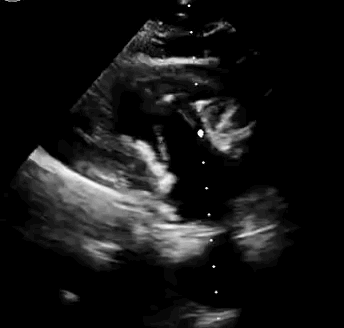

上海中山醫(yī)院葛均波院士、錢菊英院長、周達(dá)新教授、潘文志教授、潘翠珍教授、李偉教授共同完成此次臨床前研究。術(shù)后葛均波院士對Lux-Valve Plus的器械操作性能給予了高度評價,DSA和超聲影像也顯示出在本次研究中Lux-Valve Plus的安全性和有效性俱佳。

本次臨床前研究經(jīng)右側(cè)頸靜脈置入LuX-Valve Plus輸送系統(tǒng)可調(diào)彎鞘管,在DSA及超聲引導(dǎo)下將人工三尖瓣瓣膜植入到原有三尖瓣位置,利用獨(dú)特的錨定技術(shù)將人工瓣膜支架可靠固定在預(yù)定的位置。